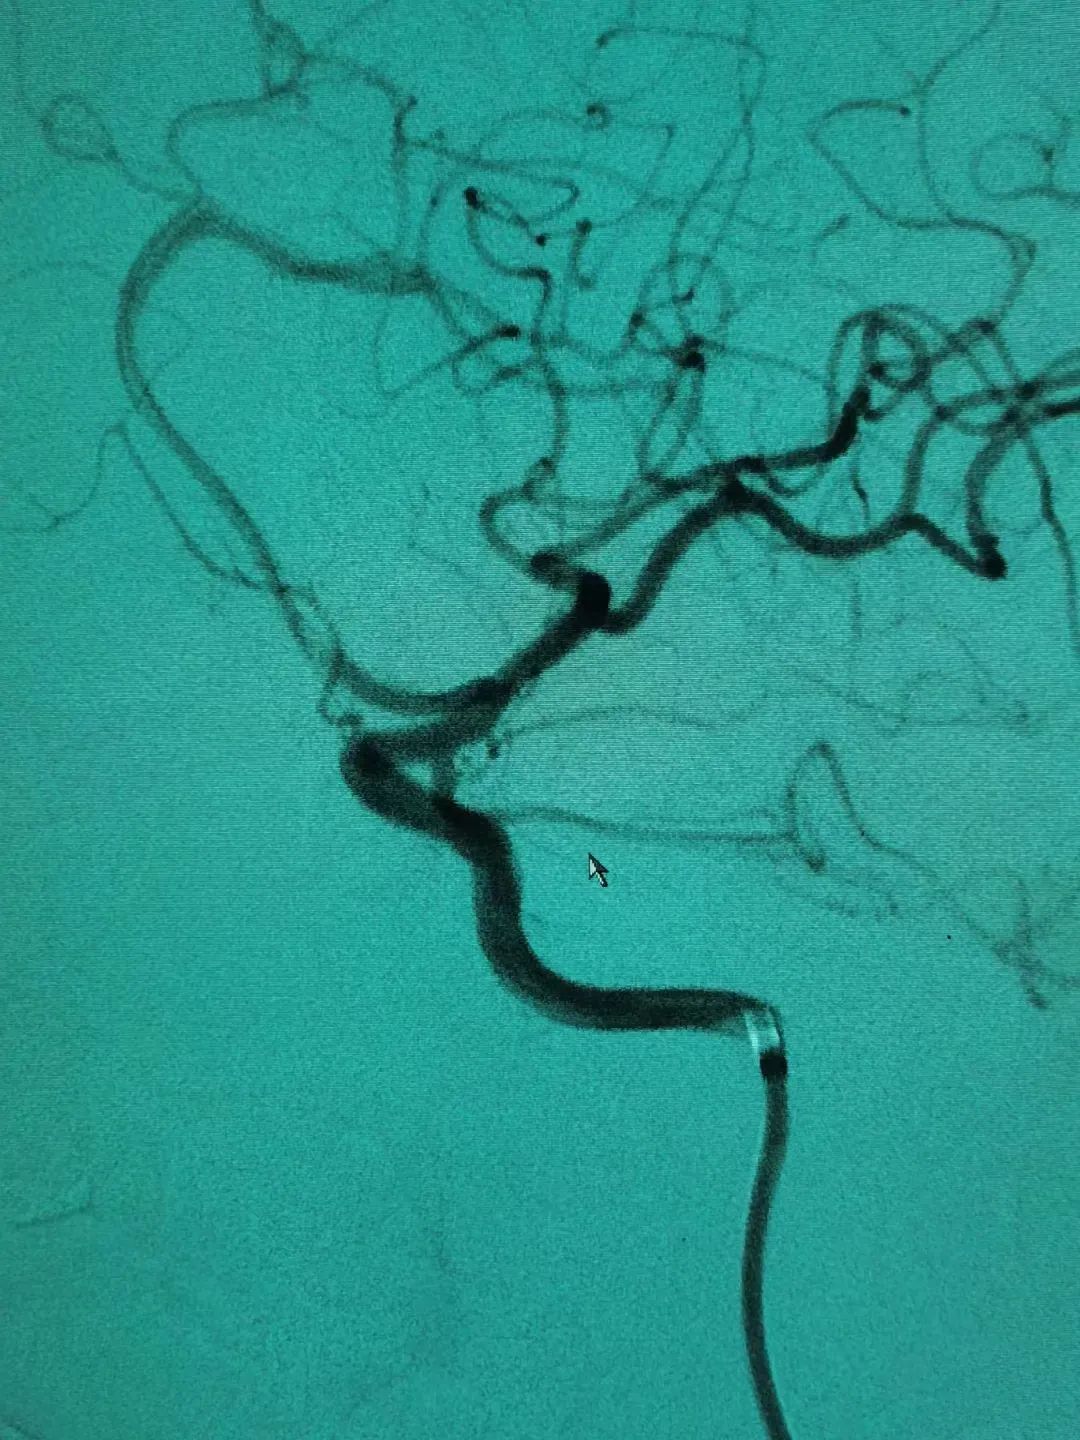

50歲的劉女士五天前深夜突發(fā)劇烈頭痛,不能忍受,伴惡心、嘔吐數(shù)次,家人急送醫(yī)院檢查。神經(jīng)外科主任施宏飛接診患者,結(jié)合患者病情、體格檢查及相關(guān)CT結(jié)果,診斷其蛛網(wǎng)膜下腔出血明確,為盡快明確患者病因,立即開(kāi)辟綠色通道行急診頭顱CTA,顯示左側(cè)后交通動(dòng)脈瘤。

得知病情后,患者家屬非常擔(dān)心,施宏飛主任與家屬耐心溝通,并建議立即行血管內(nèi)栓塞介入治療術(shù),不然動(dòng)脈瘤隨時(shí)有可能再次破裂出血威脅生命!家屬同意后,完善術(shù)前相關(guān)檢查,在全麻下行全腦血管造影術(shù)+左側(cè)后交通動(dòng)脈瘤栓塞術(shù)。術(shù)中施宏飛主任和王明義副主任醫(yī)師通力協(xié)作,在麻醉科、介入科醫(yī)護(hù)技團(tuán)隊(duì)的密切配合下,用縝密的治療方案、精湛的介入技術(shù)成功為患者“拆除炸彈”!

1、介入栓塞:通過(guò)股動(dòng)脈插管,在DSA機(jī)器引導(dǎo)下將細(xì)小的導(dǎo)管系統(tǒng)經(jīng)過(guò)血管送達(dá)顱內(nèi),把彈簧圈填入瘤腔,達(dá)到防止再出血的目的,是微創(chuàng)治療手段。